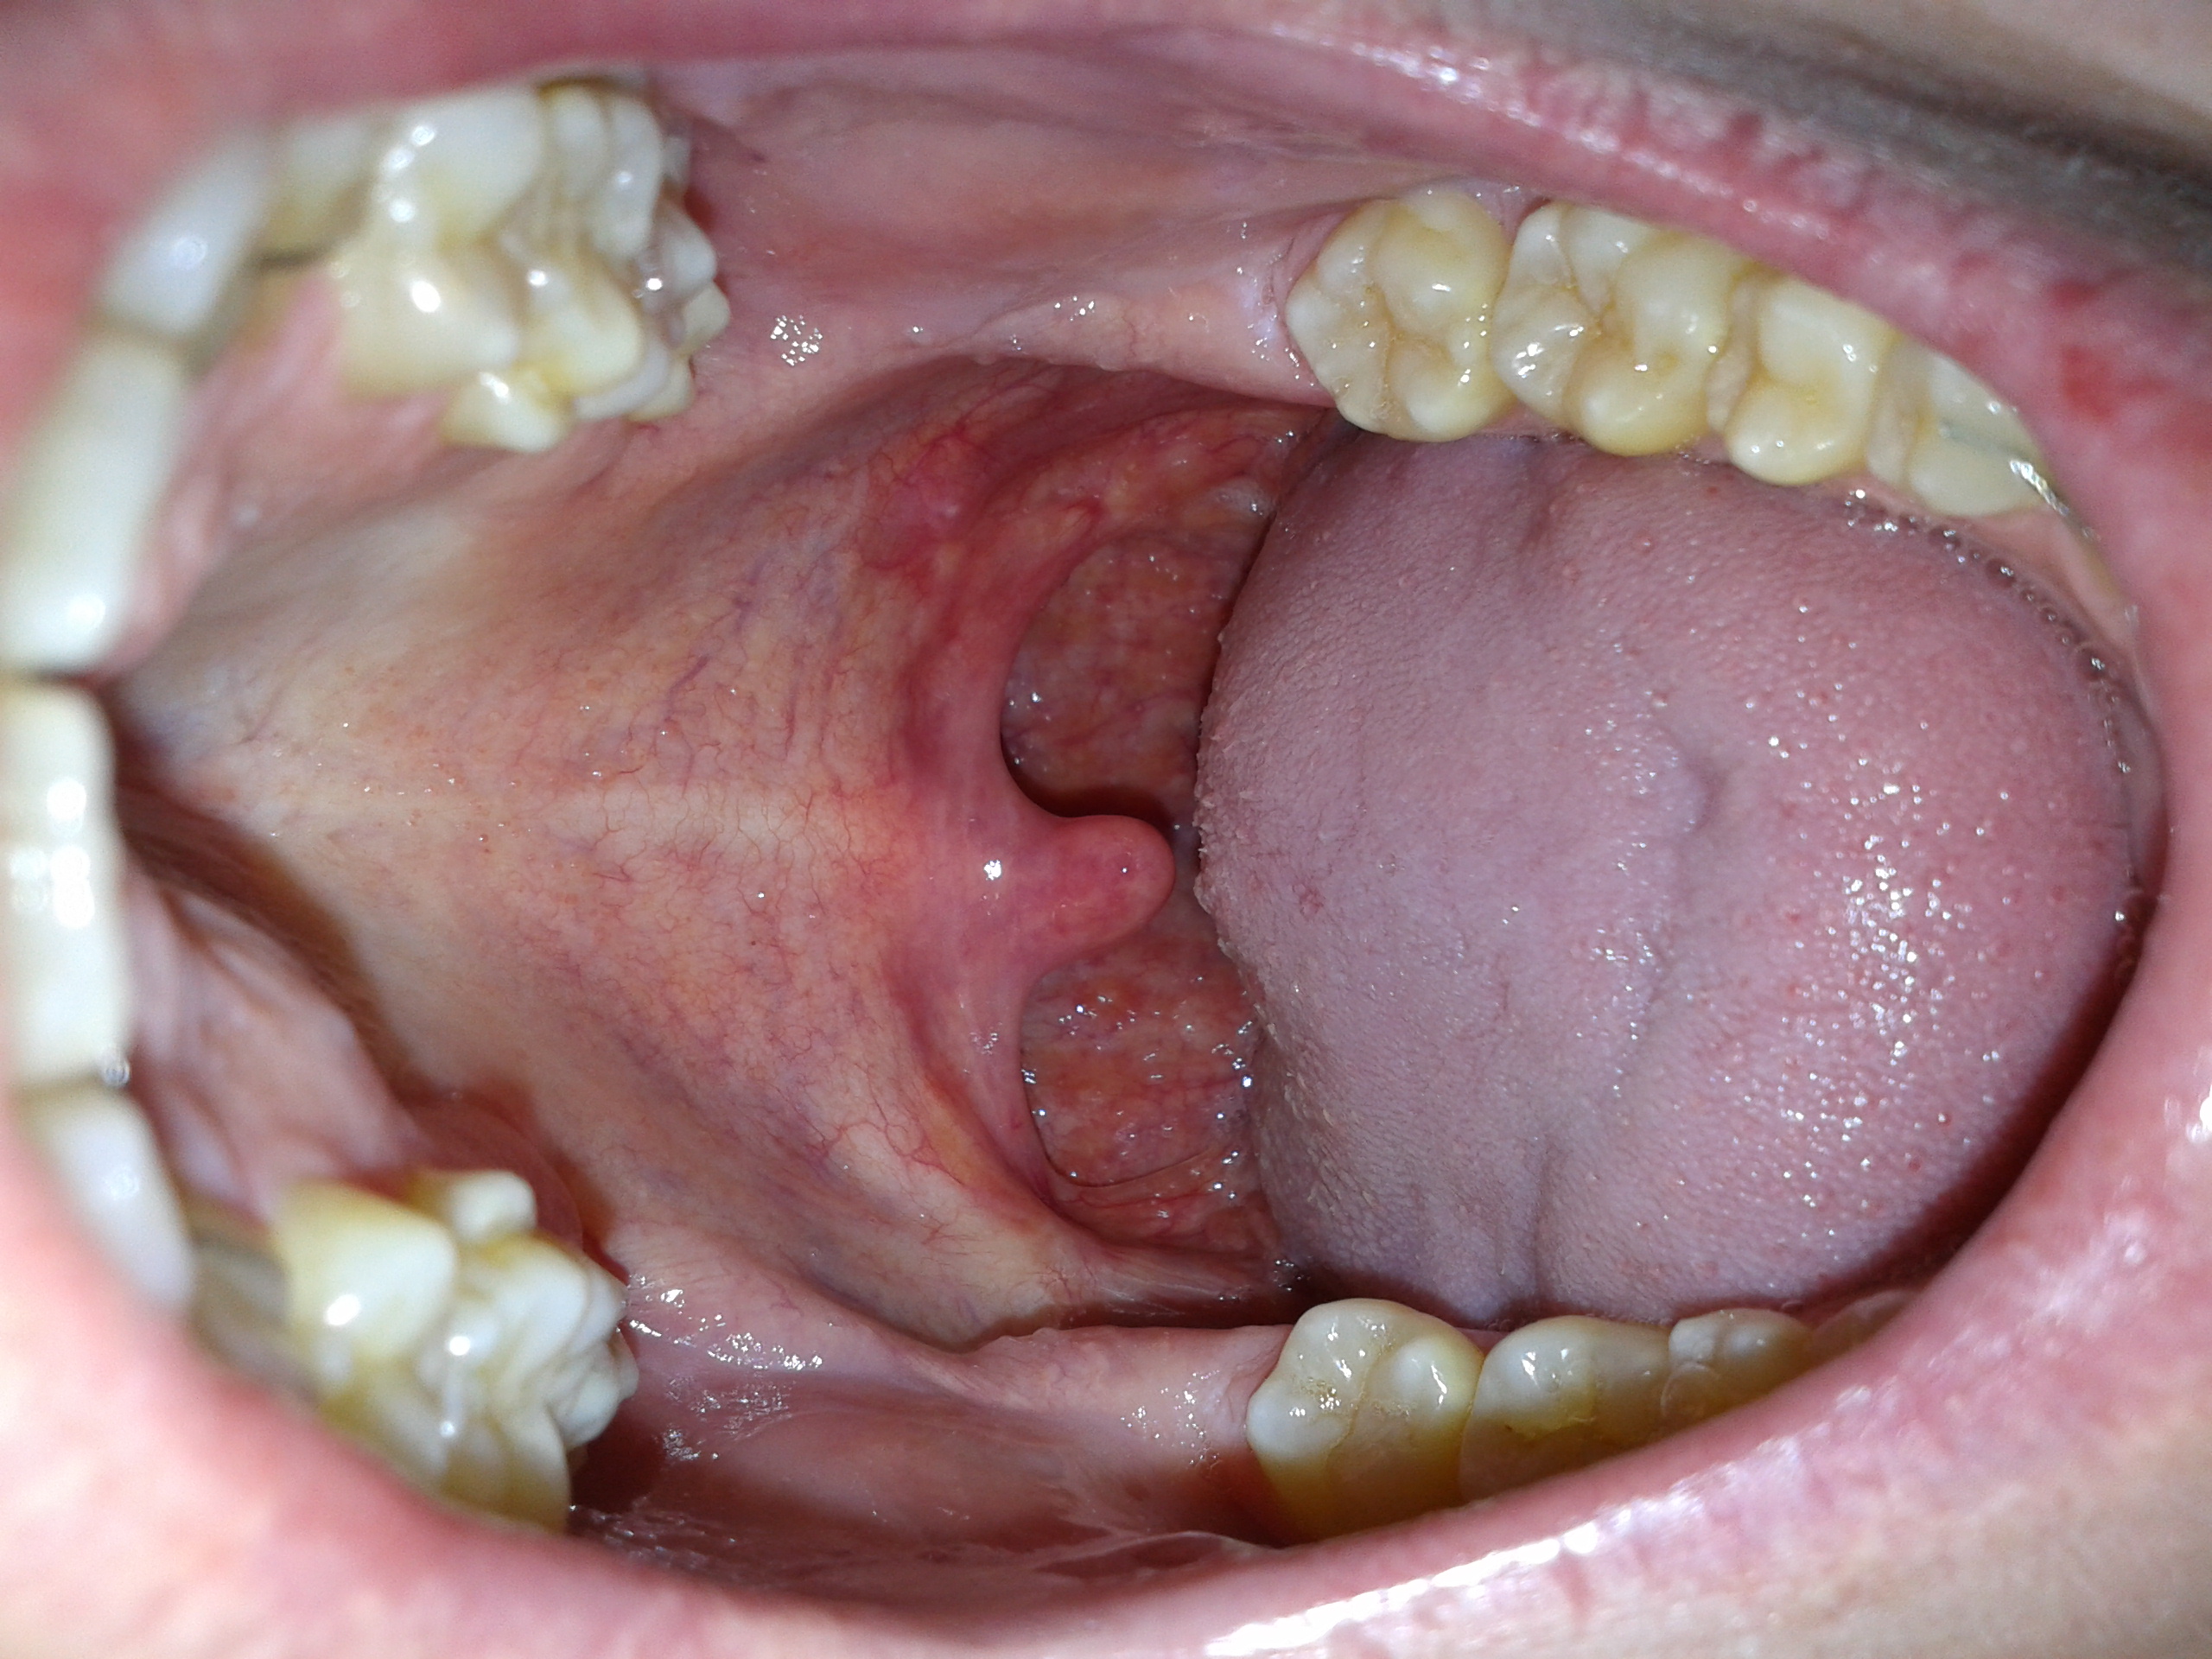

Bei den ersten Anzeichen von weißen Belägen im Mund sollten Sie sofort reagieren und Ihren Arzt aufsuchen. Zur Behandlung von Mundsoor eignen sich miconazolhaltige und besonders haftfähige Mundgels wie z.B. InfectoSoor Mundgel. Eine gute Mundhygiene beugt dem Risiko einer Pilzinfektion vor.. Im Normalfall sind Hefepilze so gut wie harmlos und führen zu keinen Symptomen oder Beschwerden. Sind unser Immunsystem oder unsere Haut und/oder Schleimhaut jedoch wund und verletzt, können sie sich vermehren und zu einer Infektion führen. Passiert dies in unserem Mund, dann sprechen wir von einem Mundsoor, den wir auch als Mundpilz bezeichnen.

Entzündung im Mund. Eine Entzündung im Mund ohne Bläschenbildung oder die Entstehung von Belägen betrifft meistens die Mundschleimhaut oder das Zahnfleisch. Zu erkennen ist sie häufig an Rötungen, Schwellungen und Schmerzempfindlichkeit, mitunter kann die betroffene Stelle auch bluten. Eine Mundschleimhautentzündung wird als Stomatitis.. Daneben löst der Pilz im Mund Symptome wie ein verändertes Geschmacksempfinden oder ein brennendes Gefühl auf der Zunge aus. Der Belag, der für das pelzige, unhygienische Gefühl sorgt, lässt sich mit geeigneten Instrumenten abstreifen. Darunter finden sich oftmals gerötete Läsionen, die ihrerseits für die Schmerzen und damit auch für.